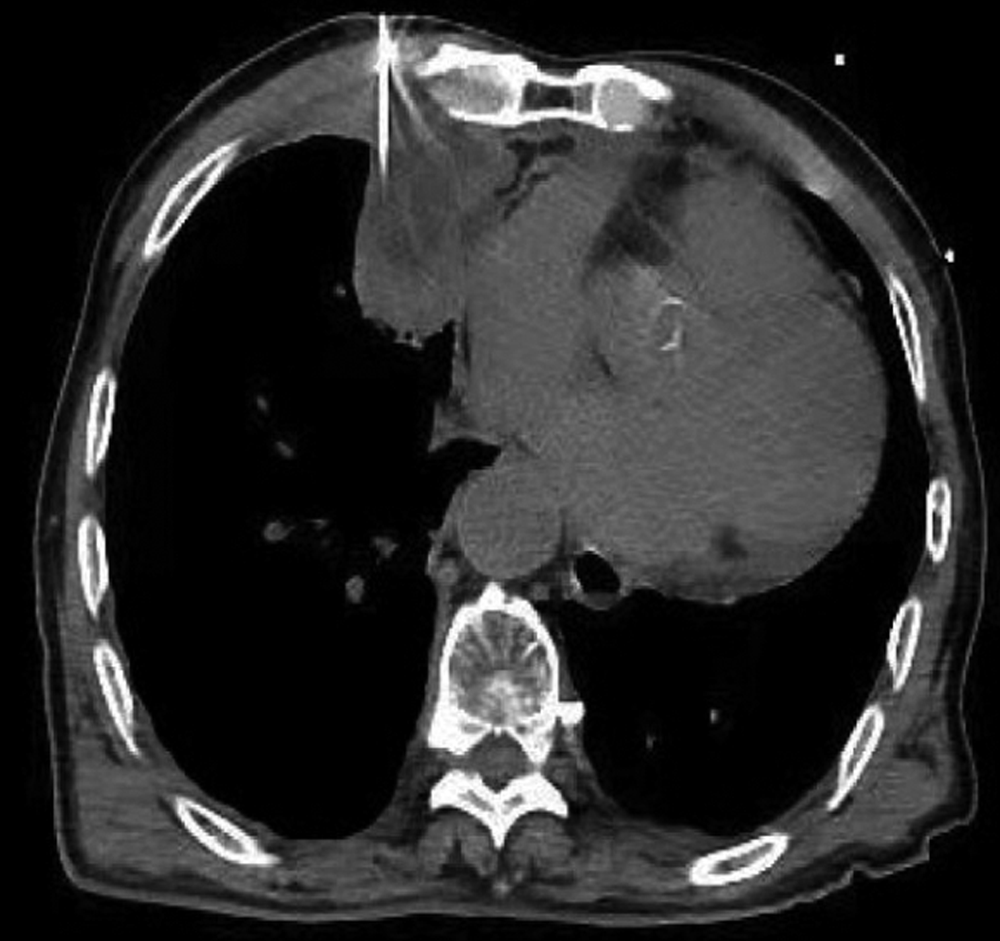

Yamamoto N, Watanabe T, Yamada K, et al. Efficacy and safety of ultrasound (US) guided percutaneous needle biopsy for peripheral lung or pleural lesion: comparison with computed tomography (CT) guided needle biopsy[J]. J Thorac Dis, 2019, 11(3): 936-943. DOI: 10.21037/jtd.2019.01.88.

Jarmakani M, Duguay S, Rust K, et al. Ultrasound versus computed tomographic guidance for percutaneous biopsy of chest lesions[J]. J Ultrasound Med, 2016, 35(9): 1865-1872. DOI: 10.7863/ultra.15.10029.

Park J, Park B, Lim JK, et al. Ultrasound-guided percutaneous needle biopsy for small pleural lesions: diagnostic yield and impact of CT and ultrasound characteristics[J]. AJR Am J Roentgenol, 2021, 217(3): 699-706. DOI: 10.2214/AJR.20.24120.